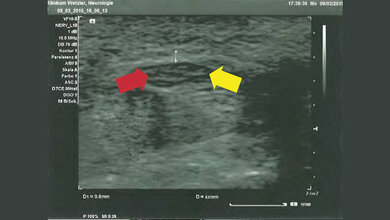

In einer aktuellen Studie der Universitätsmedizin Leipzig mit Unterstützung des Helmholtz-Instituts für Metabolismus-, Adipositas- und Gefäßforschung (HI-MAG) fanden Forscherinnen und Forscher heraus, dass die Qualität des Ultraschalls bei Leber- und Nierenuntersuchungen bei Patientinnen und Patienten mit Adipositas deutlich beeinträchtigt ist. „Die Ergebnisse zeigten: Je höher der Body-Mass-Index der Teilnehmenden war, desto schlechter war auch die Bildqualität des Ultraschalls. Außerdem wurde deutlich: Moderne Ultraschallsonden mit der sogenannten Matrixtechnologie verbessern die Qualität der Ultraschallabbildung“, erklärt Prof. Dr. Thomas Karlas, Studienleiter und korrespondierender Autor der aktuellen Publikation. Die Matrixsonden besitzen eine verbesserte Sende- und Empfangstechnologie und erreichen dadurch eine höhere Eindringtiefe in das Gewebe. Somit kann eine bessere diagnostische Genauigkeit bei Risikopatientinnen und -patienten erreicht werden. Bislang gab es noch keine ausreichende wissenschaftliche Bestätigung der Leistungsfähigkeit der Matrixsonden bei Personen mit Übergewicht.

Die aktuellen Daten zeigen, dass die relativ teuren Spezialsonden für Ultraschallgeräte einen relevanten Mehrwert bieten können. Bei den 40 Teilnehmerinnen und Teilnehmern der Studie wurde eine hoch standardisierte Ultraschalluntersuchung des Bauchraums mit drei verschiedenen Sonden, Standardsonde versus zwei Hochleistungssonden, durchgeführt. Untersucht wurden die Leber und die rechte Niere bei Menschen mit verschiedenen Graden des Übergewichts. Die Qualität der Ultraschalluntersuchung wurde anhand eines Punktescores bewertet.